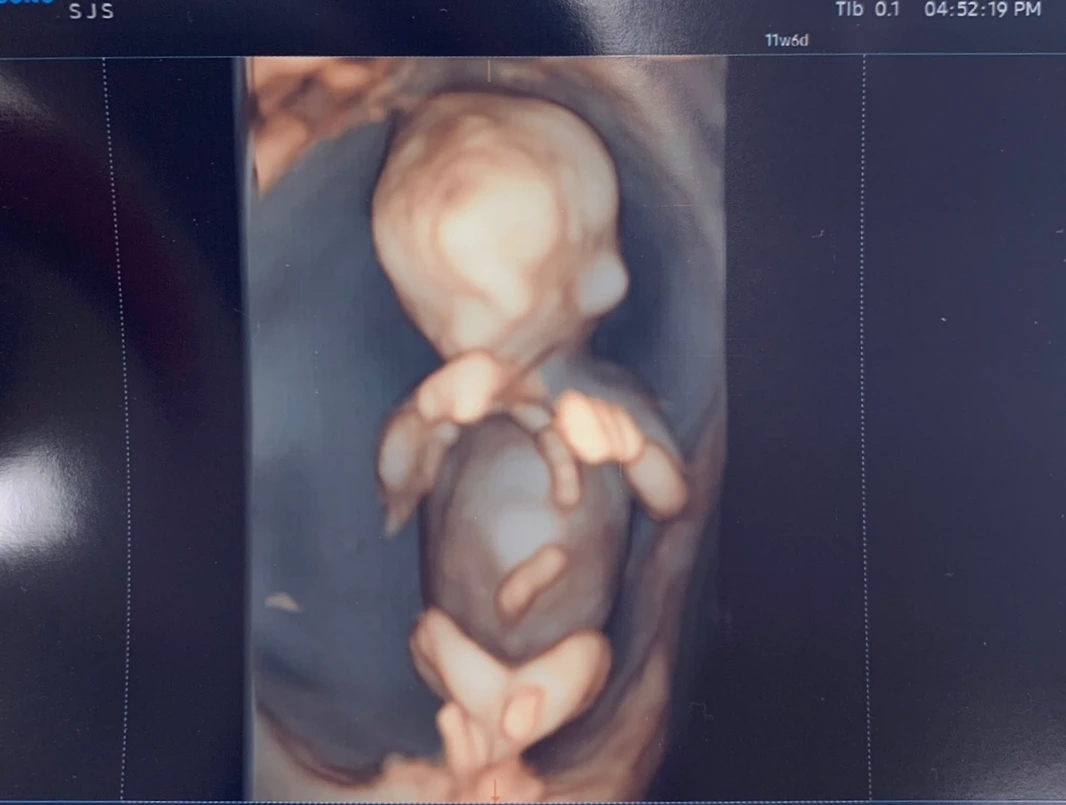

KakaoTalk_Photo_2022-11-13-13-08-40.jpeg 12주차 황금이